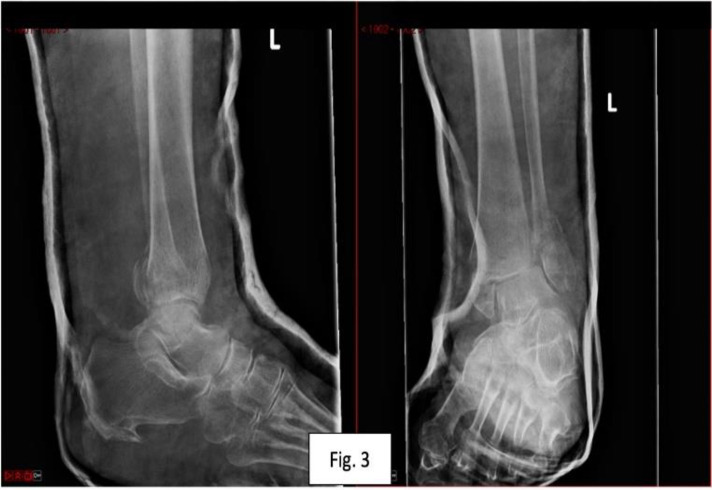

Here we present a novel adaptation of the previously described fibula pro-tibial fixation in a case requiring salvage fixation of a bimalleolar ankle fracture in an osteoporotic patient. Unstable osteoporotic ankle fractures are a challenging injury to manage and typically occur in a frail and comorbid subgroup of patients. Various techniques have been described in the evolution of managing these injuries, e.g. hindfoot nailing and anatomical locking plates, however in this uniquely challenging case a novel strategy was required to mitigate bone loss in the distal fibular fracture fragment. There is some evidence to suggest fibular protibial fixation offers a lower complication profile to its alternatives. The novel use of distal fibula pro-tibial screws offers a new alternative to hindfoot nailing of bimalleolar ankle fracture in osteoporotic bone with compromised distal fibular fragment bone purchase. Further research is required to investigate the compatibility of this technique with early weightbearing.

Abstract Image